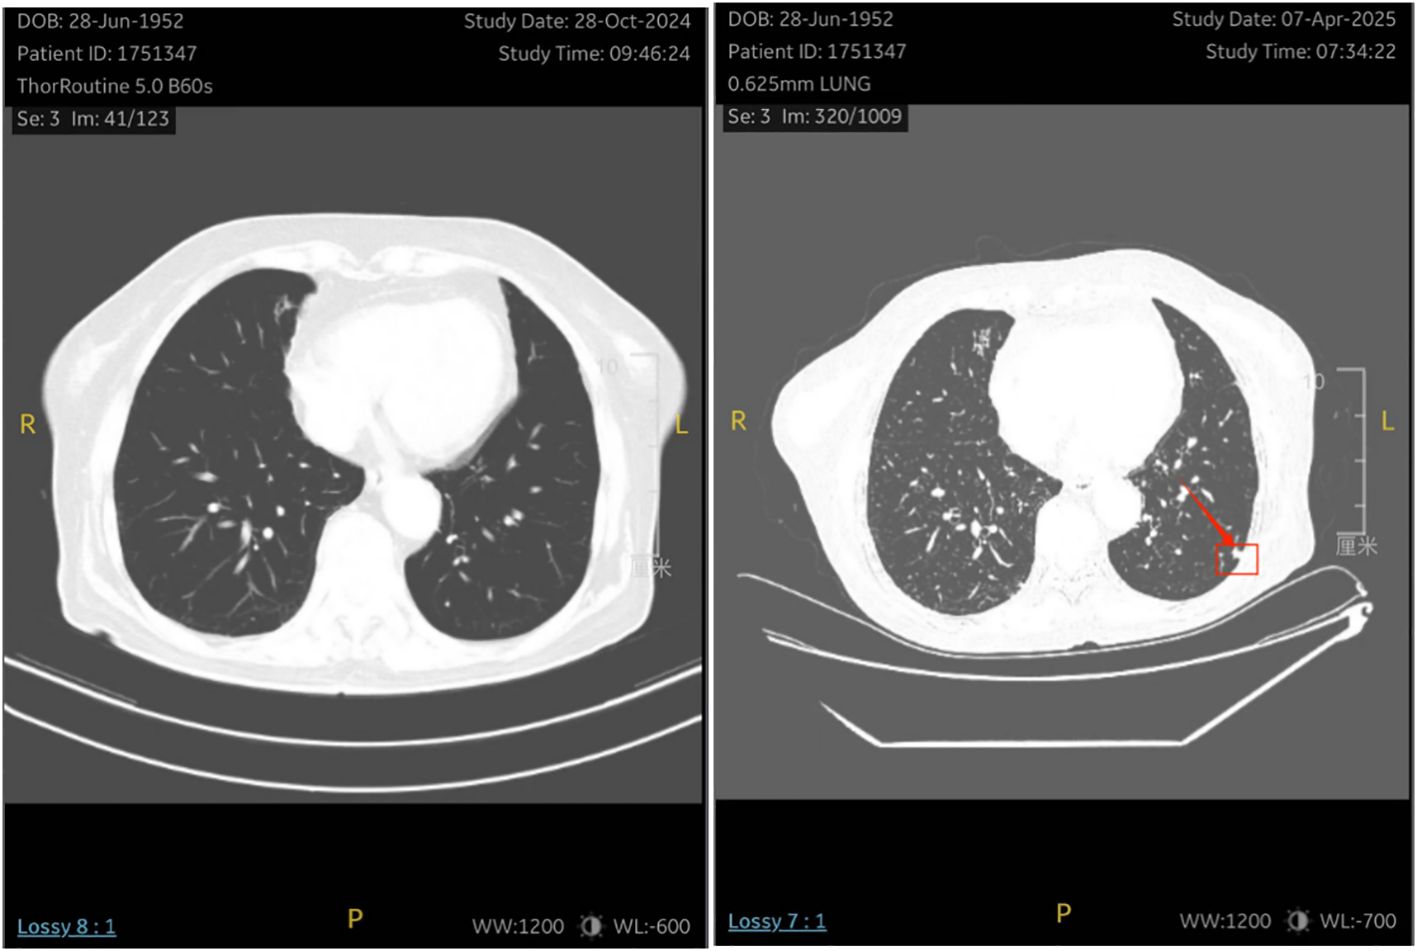

One month after chemotherapy, the patient developed dysuria. Ultrasound showed right hydronephrosis, and CT suggested possible metastatic nodules in the left pelvic peritoneum. PET/CT revealed a new hypermetabolic soft-tissue lesion (SUVmax ≈4.3) in the mesentery (Figure 5), indicating recurrence. Serum AFP was measured at 3.16 ng/mL (reference range 0–7 ng/mL). Given these examination results, the possibility of metastasis and recurrence was considered. The patient requested continued observation without treatment. On April 7, 2025, chest CT detected multiple pulmonary nodules suggestive of metastasis (Figure 6), though AFP remained normal. Multidisciplinary consultation recommended paclitaxel (240 mg/m²) + carboplatin (AUC = 5) + pembrolizumab (2 mg/kg).

Figure 6. The patient underwent a re-examination of the chest CT on April 7, 2025, which revealed multiple small nodules in the lungs . It is considered that there might be metastatic tumors.